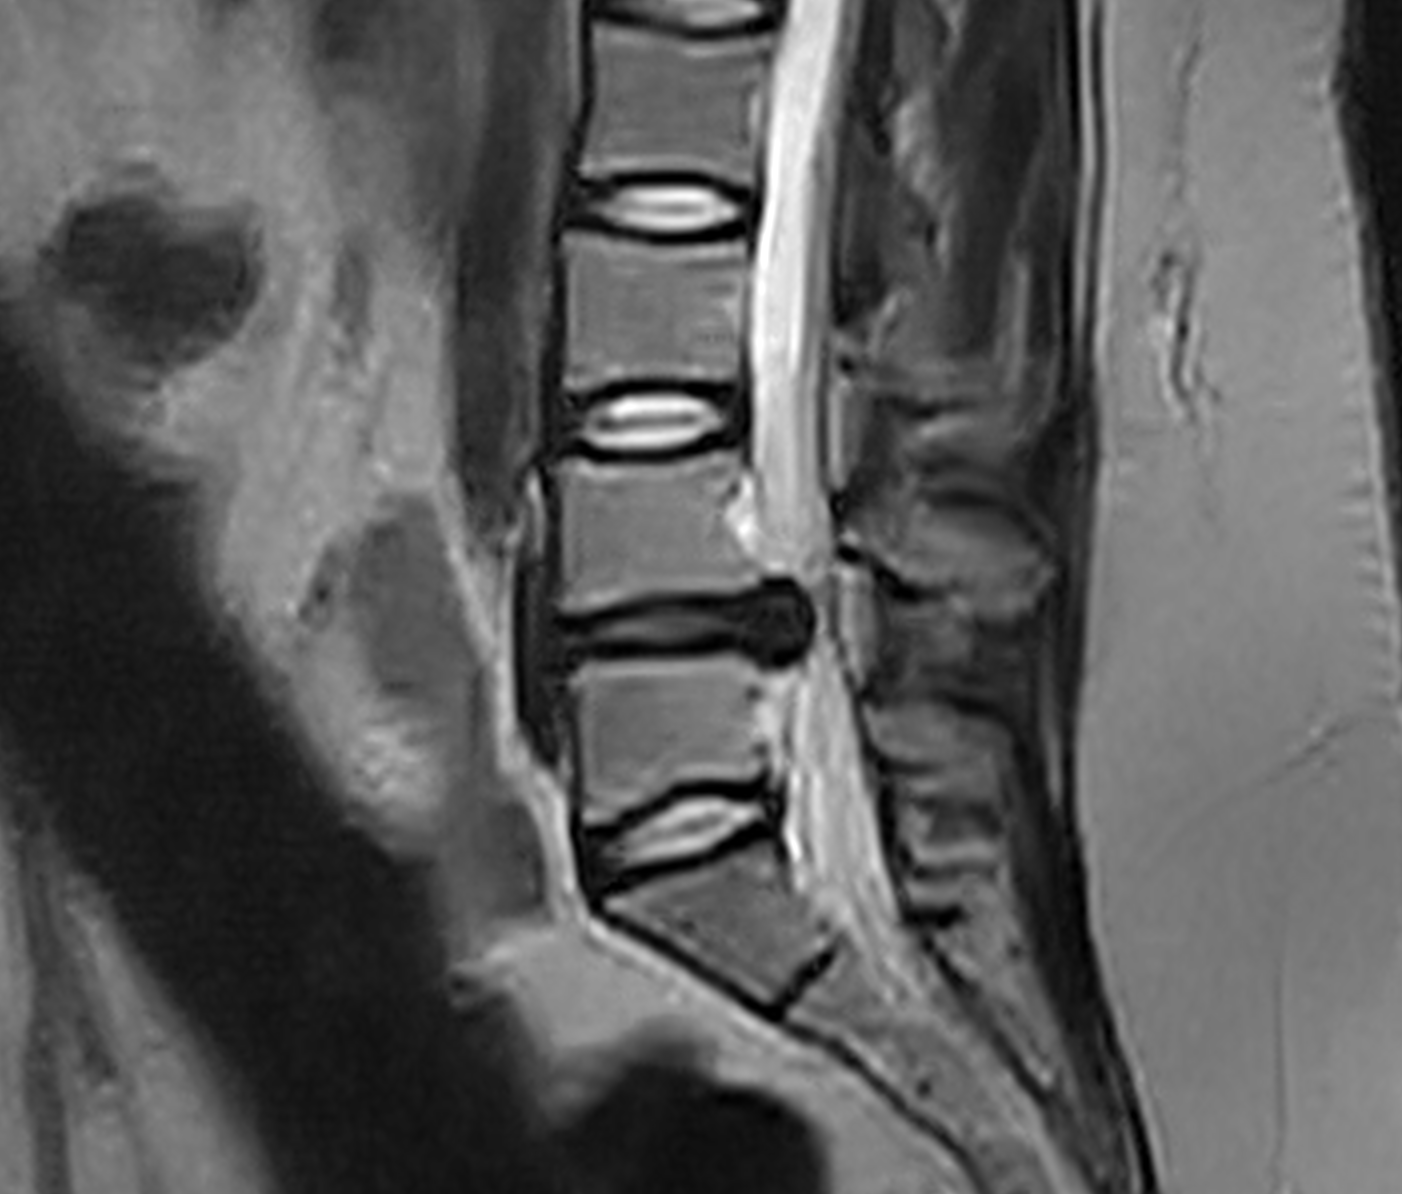

Gracias a un equipo multidisciplinar altamente cualificado y a la utilización de las técnicas más avanzadas, el Grupo IENSA se ha consolidado como referente nacional en el abordaje de la hernia discal lumbar. Nuestro objetivo principal es mejorar la calidad de vida de los pacientes, minimizando el dolor y recuperando la movilidad en el menor tiempo posible. Para el estudio y la toma de decisión correcta en estos pacientes en necesario la valoración de un Neurocirujano, la valoración por neurofisiología y la interpretación de las pruebas de imagen con una congruencia con la clínica del paciente.

La cifra de más de 2.800 pacientes intervenidos de hernia discal lumbar es un claro reflejo de la confianza que depositan los enfermos en nuestro grupo y del compromiso de IENSA con la salud lumbar. Cada caso de hernia discal lumbar es estudiado de forma personalizada, aplicando el tratamiento más adecuado para cada paciente, ya sea mediante cirugía mínimamente invasiva, rehabilitación o terapias complementarias. Hasta un 43% de los casos son dados de alta en el mismo día de la intervención y otro 54% al día siguiente, únicamente un 2% se quedan ingresados más de 1 día.

El Grupo IENSA apuesta firmemente por la innovación y la formación continua de sus especialistas, lo que nos permite estar a la vanguardia en el tratamiento de la hernia discal lumbar, realizándose intervenciones mediante técnica Mínimamente Invasiva, Endoscopia, Microcirugía, o termo coagulación Intradiscal con láser. Nuestra experiencia y la satisfacción de nuestros pacientes nos motivan a seguir avanzando en la búsqueda de las mejores soluciones para esta dolencia.